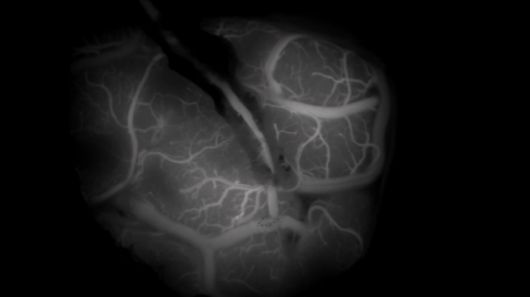

EBS '명의' 스틸컷. [사진=EBS] |